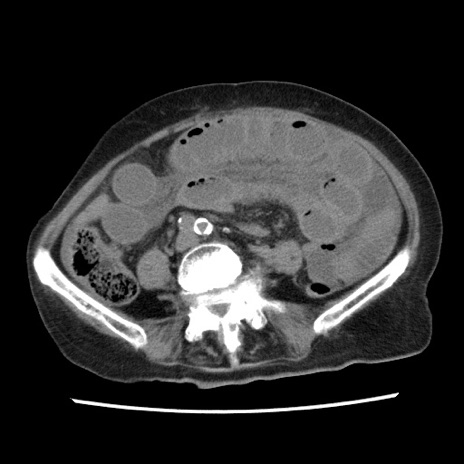

冠状断像

矢状断像

【症例】80歳代女性

【主訴】腹痛

【現病歴】8時間前から腹痛あり来院。

【既往歴】糖尿病、脂質異常症、子宮体癌にて子宮全摘術

【身体所見】意識清明・会話良好だが腹痛で苦悶様、全腹部にわたって反跳痛と圧痛あり

【データ】WBC 13600、CRP 0.14、LDH 224、CK 90